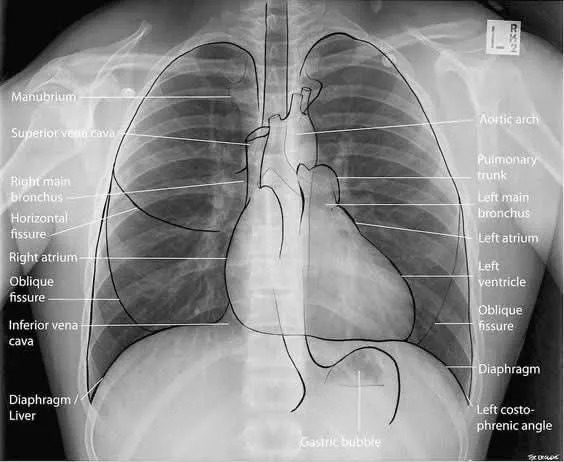

Chest X-Ray